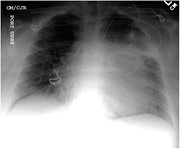

Blunt aortic trauma in a patient with the Ehlers–Danlos syndrome type VI

Marco Yat Hang Yung and others

Journal of Surgical Case Reports, Volume 2016, Issue 3, March 2016, rjw026, https://doi.org/10.1093/jscr/rjw026